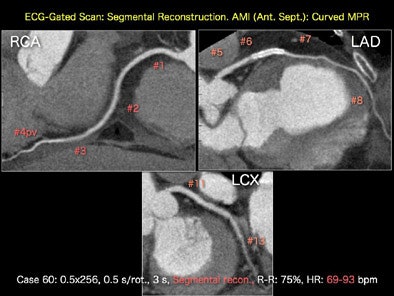

![]() |

| Segmental reconstructions of an ECG-gated scan shows high-resolution images of (clockwise from top) the right coronary artery, left anterior descending artery, and left circumflex artery acquired on a 256-detector CT scanner. All images courtesy of Dr. Kazuhiro Katada. |

Katada's group has used its 256-slice system to produce 4D images (3D cine movies) of the heart. The system is particularly good at stent visualization, as well as detecting soft plaques. As a work-in-progress, the group is developing prospectively gated multisegmental scan and reconstruction, with temporal resolution of 67 msec.